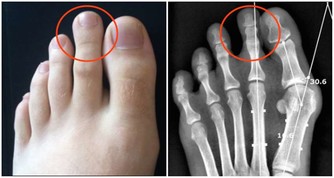

直腸、肛門、結腸等距離肛門較近部位的出血,如痔瘡、腸息肉、直腸脫垂、肛裂等導致的出血。

出現血便,普通人難以輕易判斷,很多人往往誤以為只是痔瘡引起的,不當回事。然而,便血也是腸惡性腫瘤的早期信號。

因此,便血病人最好到醫院明確病因,進行詳細的專科體檢(如肛門指檢、一次性肛門鏡檢查等)。